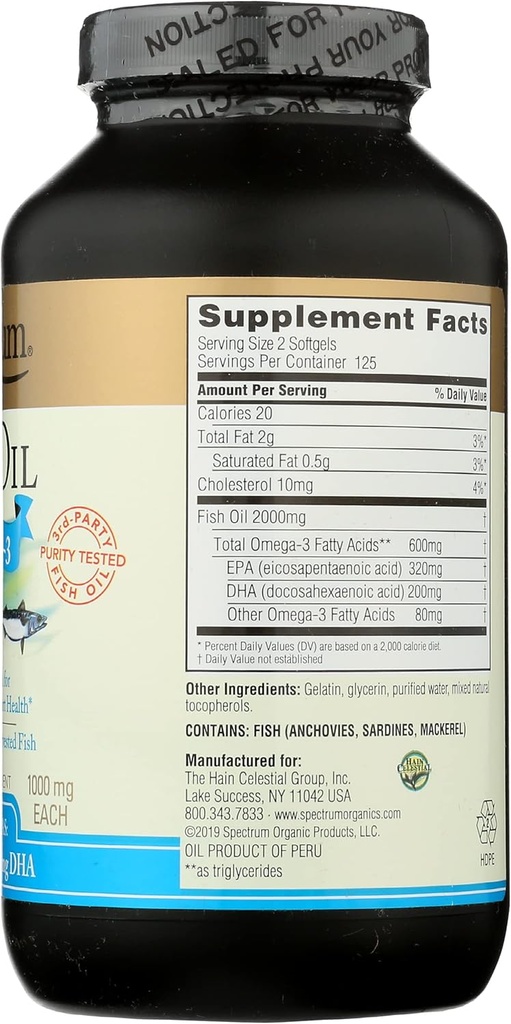

Fish oil (from anchovies, sardines and mackerel or a combination thereof), mixed natural tocopherols. Softgel (gelatin, water, glycerin).

REFRIGERATE AFTER OPENING. Suggested Serving: 2 softgels daily with food. Consult a healthcare practitioner for your individual needs.

| Ingredients | Water, Fish Oil (from Anchovies, Glycerin)., Sardines And Mackerel Or A Combination Thereof), Mixed Natural Tocopherols. Softgel (gelatin |

| Item Weight | 13.12 Ounces |

| Item Dimensions L X W X H | 3.15 X 3.15 X 6.15 Inches |

| Special Ingredients | Eicosapentaenoic Acid |

| Item Form | Softgel |

| Unit Count | 250 Count |